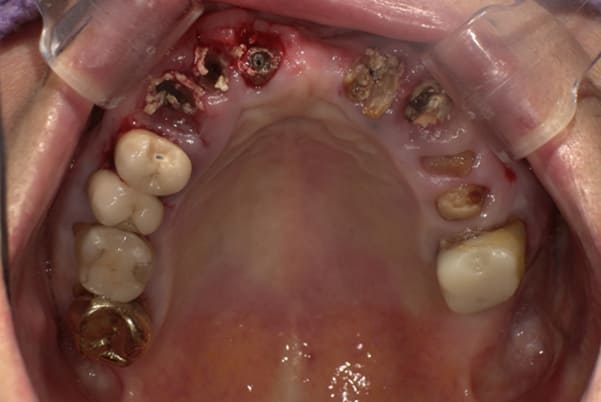

上顎治療前

根のみの7本は虫歯にもなっており歯肉は腫れあがっています。

残りの歯もレントゲンで重度の歯周炎によりぐらぐらな状態でした。